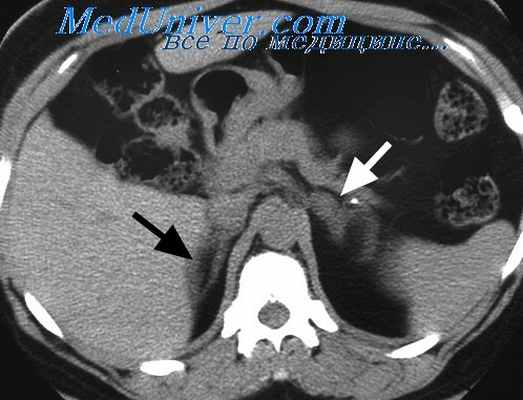

Прямым подтверждением наличия первичной надпочечниковой недостаточности является резкое повышение уровня АКТГ в плазме крови, при вторичной — его снижение. С целью диагностики гипоальдостеронизма определяют содержание альдостерона и ренина в плазме крови. При первичной надпочечниковой недостаточности содержание альдостерона снижено или находится на нижней границе нормы, а уровень ренина повышается. Визуализация надпочечников (УЗИ, компьютерная томография) также позволяет уточнить форму надпочечниковой недостаточности.